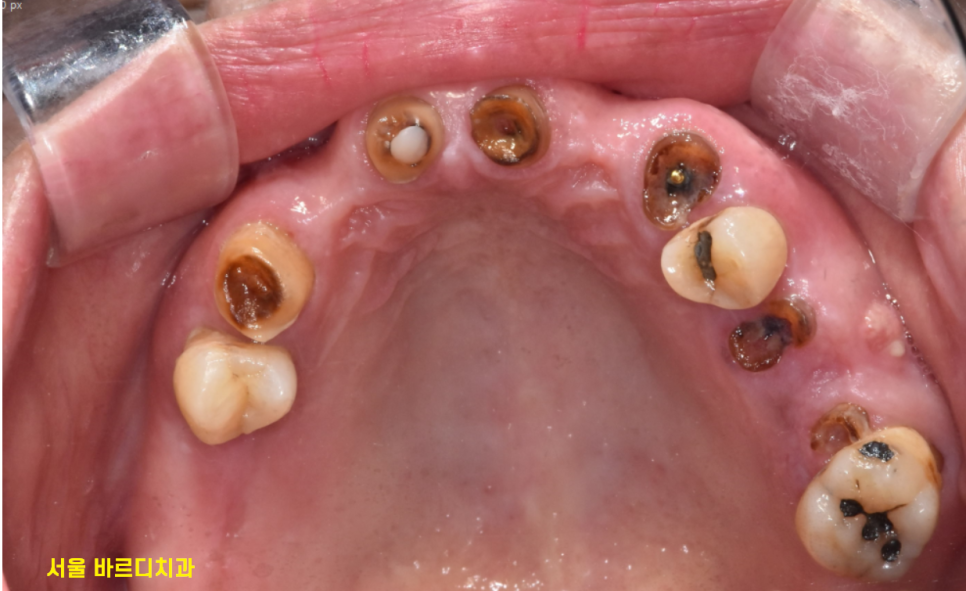

입안 사진 촬영한 것으로도

확인할 수 있지만

230817

최신 디지털 기능을 적극 활용하는데요.

스캐너 기계를 사용하여

입안 그대로를 옮겨두는거죠~

사진은 평면적이라 입안 상태 재현에 한계가 있습니다.

침이나 이물질 등에 의하여

가려진 부분이 있을 수 있고요